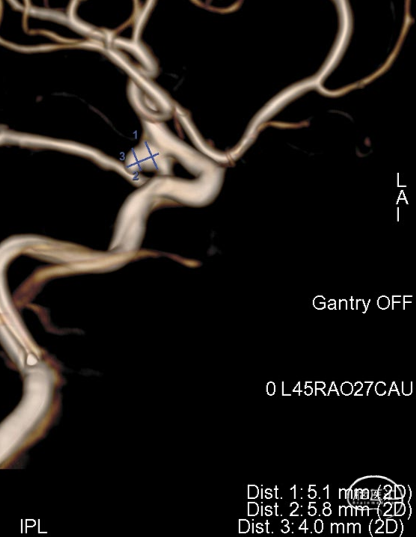

DSA:右侧颈内动脉后交通动脉起始段动脉瘤

3D测量动脉瘤:宽5.8mm,深5.1mm,SL6x3

VIA21塑形:J-5(70)-10(90)

侧位

调整解脱,后交通动脉通畅,子瘤内造影剂滞留

术后即刻造影